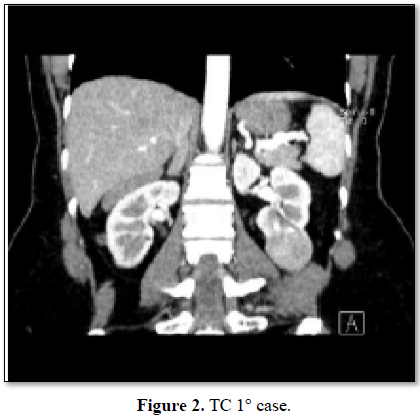

In this study we have chosen 3 patients and through the RENAL SCORE we have planned the procedure in a multidisciplinary team. The first patient is a 46 years old woman, with a tumor of 6.2 cm, entirely exophytic, localized on the lower pole of the left kidney. She has no significant comorbidity. She has been staged with TC chest-abdomen, without evidence of venous thrombus or metastasis (cT1b; N0; V0; M0). The second patient is a 64 years old woman, with a tumor of 4.1 cm, partially exophytic, localized on the superior pole of the right kidney. In anamnesis she has hypertension, obesity and hepatopathy HCV+. She has been staged with TC chest-abdomen, without evidence of venous thrombus or metastasis (cT1b; N0; V0; M0). The third patient is a 55 years old man, with a tumor of 4.8 cm, almost entirely exophytic and near to collecting system (5 mm), of the superior pole of the right kidney. In anamnesis he has only GERD. He has been staged with TC chest-abdomen, without evidence of venous thrombus or metastasis (cT1b; N0; V0; M0). At first renal arteriography is made to visualize the arterial vascularization, focused on the tumoral artery that is catheterized super selectively. The tumor and its artery is embolized with Onyx. The second time of the procedure performed is the RAPN.

In all patients the total operative time and the resection time of the tumor time are reduced compared to median of our center. Intraoperative bleeding is minimal and it isn’t necessary to isolate the vascular pedicle. In all procedures the time of ischemia is 0. The post-operative course has been regular (Clavien 0 in every patient). The tumor of patient 1 is a chromophobe cell renal carcinoma, the tumor of patient 2 is a papillary renal cell carcinoma type 1, the tumor of patient 3 is a clear cell renal carcinoma. In all patients’ surgical margins are negative. The complete description of the pre-operative, intraoperative and post-operative features is showed in Tables 1-3 and Figures 1 and 2.